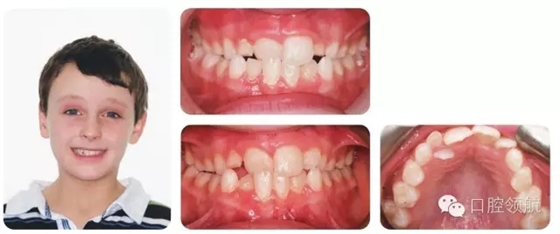

8歲的男性患者,處于混合牙列期,圖2.17上圖是當時的咬合像,下圖是1年后的咬合像(正面和牙合面)。

圖2.17

I類切牙關系,UR1反。上下牙列均有擁擠,UR2腭側(cè)錯位。